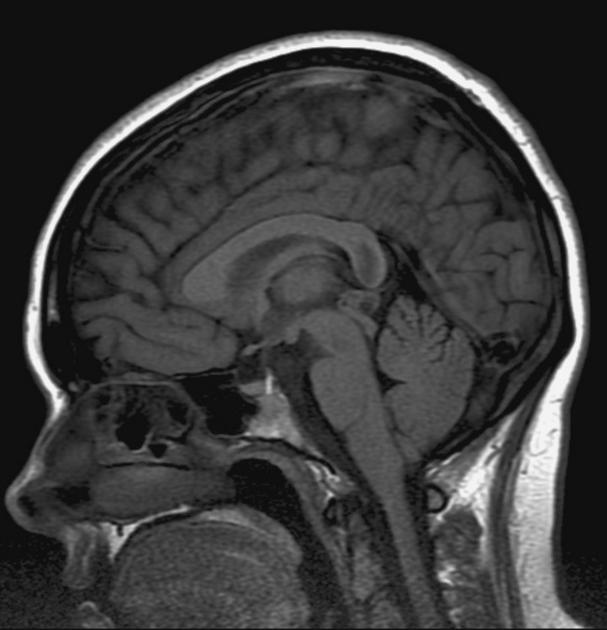

The general workup is MRI with T1/T2 images. Pineoblastomas are generally iso-enhancing on both T1 and T2, but T2 shows cystic components, at times becoming larger than the tumor itself. Surgical resection is treatment which also serves to provide tissue for diagnosis.

Pineocytoma T1 gad

Pineocytoma T1/gad